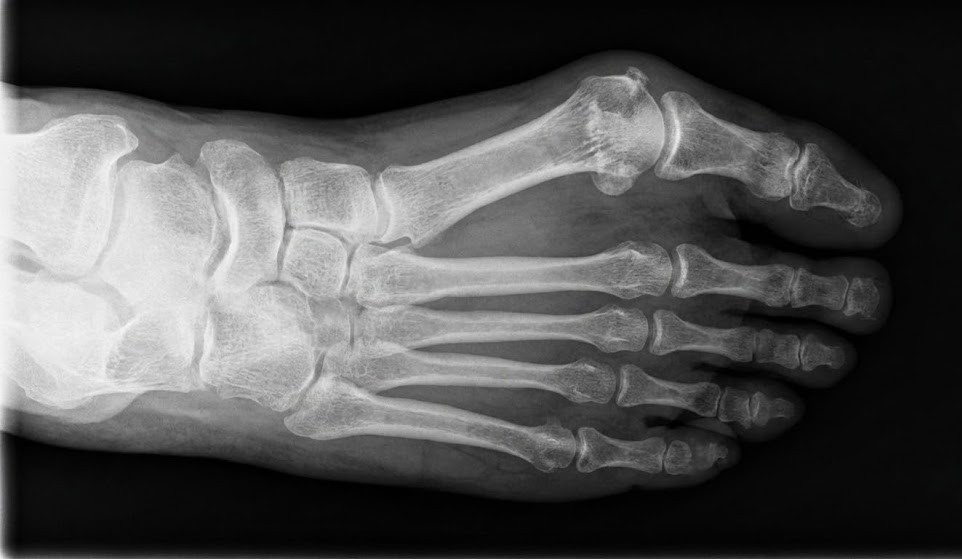

무지외반증은 엄지발가락이 두 번째 발가락 쪽으로 휘어지면서 발바닥 뼈(중족골)와의 관절이 틀어지는 질환입니다.

엄지발가락의 뿌리뼈가 안쪽으로, 발가락 끝은 바깥쪽으로 향하며 심한 경우 발 모양이 변형되고, 통증과 염증이 동반됩니다.

변형이 심해질수록 발의 균형이 깨지고, 무릎·골반·허리 통증까지 이어질 수 있습니다.

무지외반증은 단순 외형 문제로 보이지만, 발의 뼈 배열·근육 균형·보행 습관 등 복합적인 요인이 원인입니다. 따라서 각 원인을 정확히 파악해야 치료 효과가 높습니다. 강남초이스는 정밀 X-ray + 보행분석 시스템으로 변형의 원인부터 통증의 패턴까지 정확히 진단합니다.